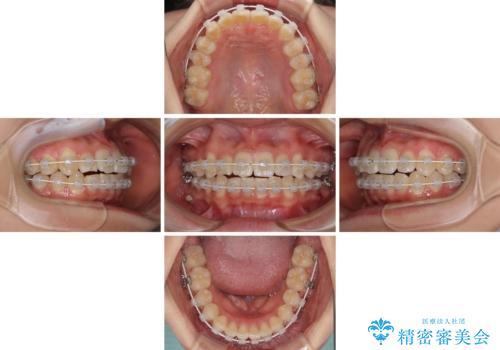

- 審美装置

- 治療期間

- 1年

- 10-30回